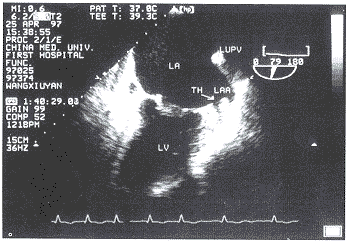

12例左心耳或左心耳和左房血栓患者均显示左心耳内或左房壁有附加血栓回声。其中多块血栓10例,单块血栓2例,最大血栓块面积17.9cm2,最小为0.62cm2。图1为血栓组患者(左图)和非血栓组患者(右图)的左心耳切面超声图像。左图中可见左心耳盲端充满强弱不等的附加回声,术后证实为血栓。右图左心耳轮廓清晰,无附加回声。

左图中可见左心耳盲端充满强弱不等的附加回声(TH)。

LA=左房,LAA=左心耳,LV=左室,LUPV=左上肺静脉,TH=血栓

图1 血栓组患者(左图)和无血栓组患者(右图)的左心耳切面超声图像